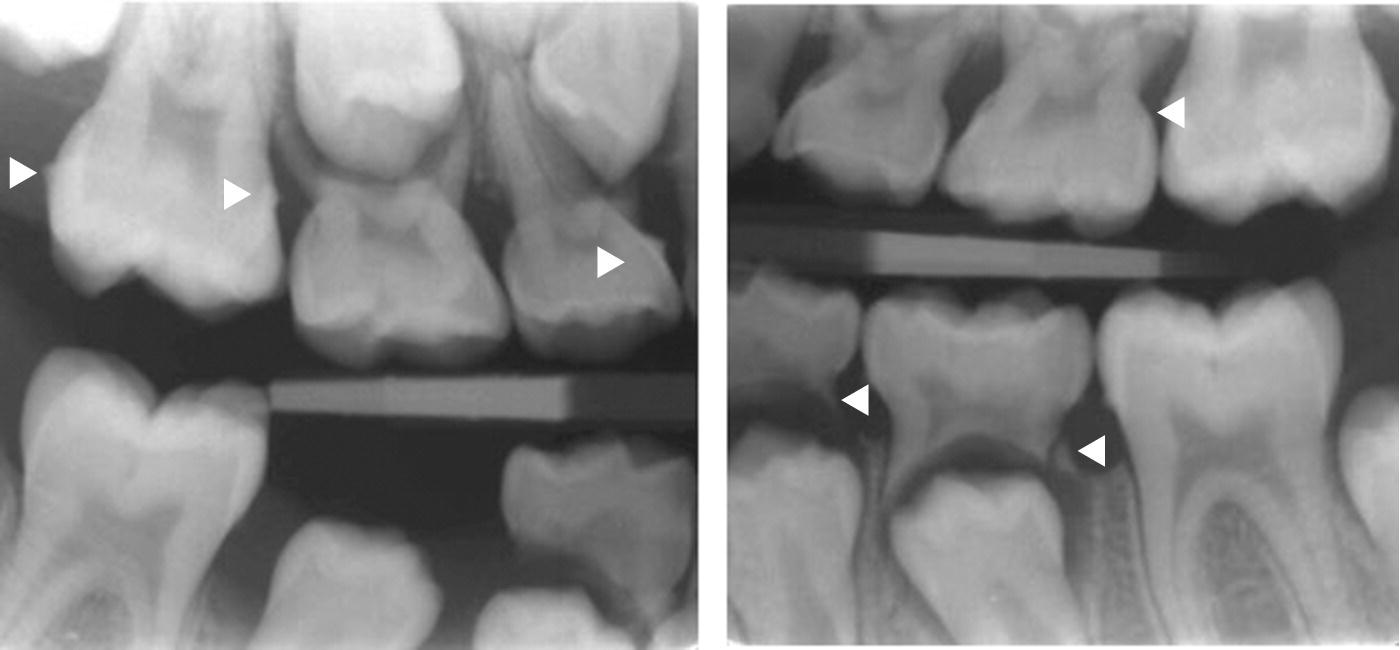

Figure 3 from Radiologic Assessment of the Periodontal Patient Dental Calculus X Ray Dental calculus represents the first fossilized record of bacterial communities as a testimony of evolutionary biology. Dental calculus shows up on the dental xray image. In addition to causing visible yellow, brown, or black deposits, they cause bad breath and bloody gums. Calcium deposits, also known as tartar or calculus, arise when plaque on the teeth hardens and thickens. Dental. Dental Calculus X Ray.